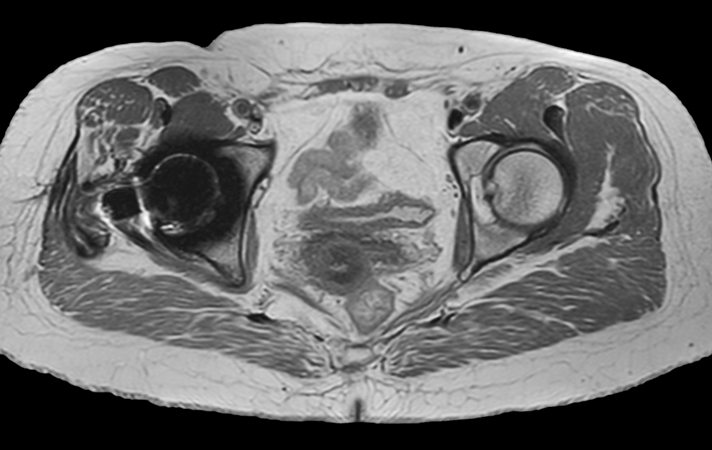

Hip imaging with metal implant

Used Solution

**Only for use with MR Safe or MR Conditional Implants by strictly following the Instructions for Use.